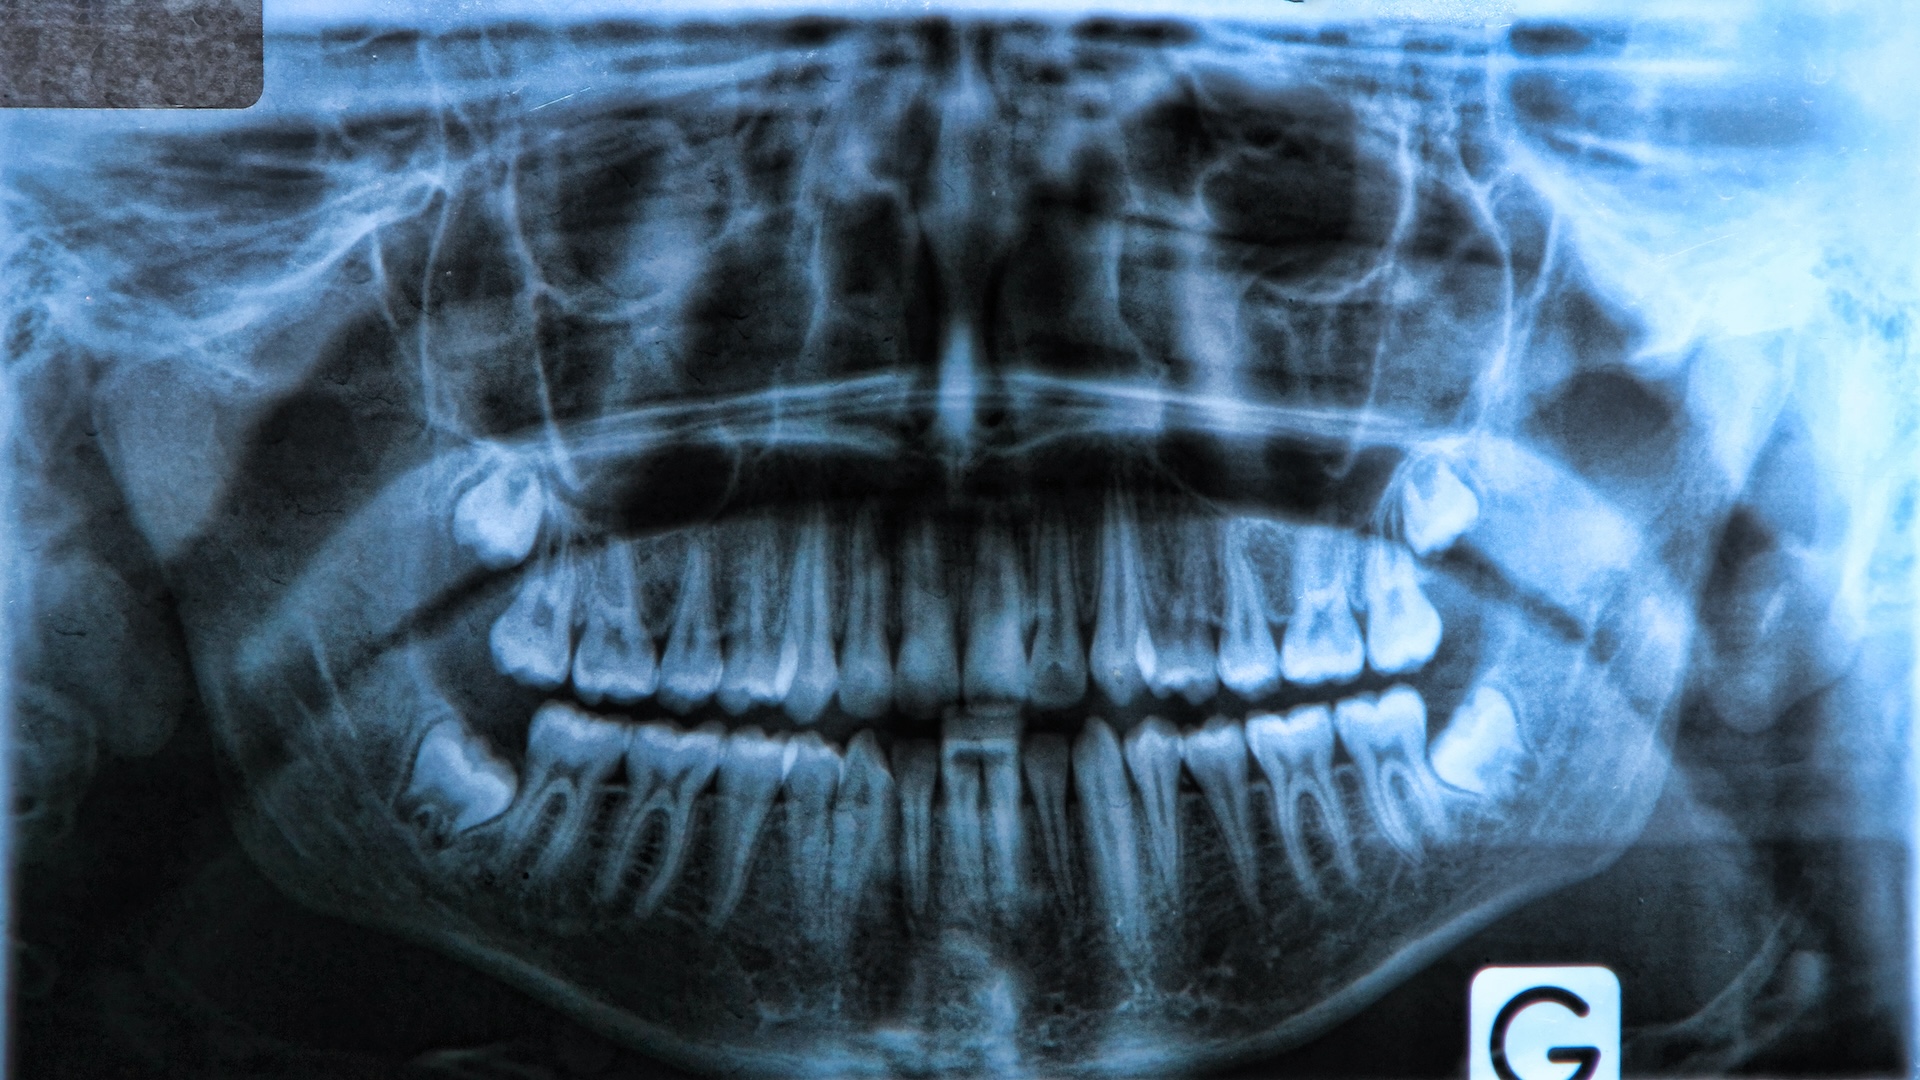

Зубы мудрости — это эволюционный «остаток», и у некоторых людей они так и не вырастают.

Согласно основному определению эволюции — изменение характеристик, которые наследуются или передаются через гены от родителей к детям, — да, люди все еще эволюционируют! Но чтобы увидеть это, нужно присмотреться.Один из очевидных примеров — зубы мудрости, те самые моляры, которые наконец-то появляются в конце подросткового или начале 20-летнего возраста. Раньше у нас были большие и сильные челюсти, потому что нам нужно было пережевывать жесткую пищу. Сегодня у некоторых людей есть мутация, из-за которой у них нет зубов мудрости. Эта мутация становится все более распространенной, потому что сейчас мы едим мягкую, приготовленную пищу и нам не нужно жевать, как это делали наши предки.

Зубы мудрости исчезают

Все больше людей лишаются зубов мудрости благодаря изменениям в нашей ДНК. Многие люди вынуждены удалять зубы мудрости, потому что они причиняют боль или не помещаются во рту. Это происходит потому, что челюсти человека в процессе эволюции уменьшились.